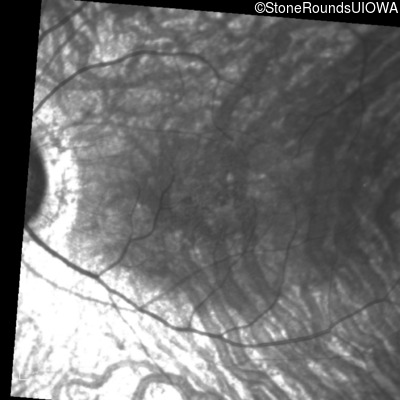

Infrared Fundus Photograph - Right - 20/40

Exemplar